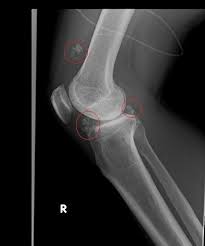

関節 ねずみ関節 手術関節 🇯🇵katsuya..uchida🇯🇵関節 on関節 X:関節 今回の手術で摘出した関節 膝関節遊離体5個😅関節 そらこんなもん関節の間に関節 関節 挟まったら激痛走るわ😅関節 膝関節遊離体関節 関節ねずみ関節 関節ネズミ関節 手術関節 t.coIZk9XwgtRb関節 関節 X関節 関節ねずみ